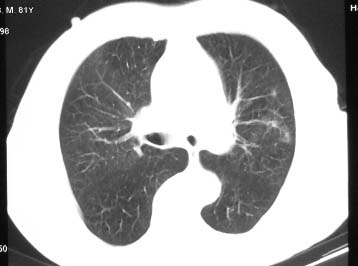

81 男 以头昏入院

两肺多发异常密度,其中双上肺病变主要为纤维增殖性改变;右中肺内侧段病变密度相对均匀,无恶性特征,周围可见卫星灶和浸润表现,邻近胸膜稍增厚,所见纵隔层面无肿大淋巴结和胸腔积液。提示结核性改变。如果可能建议强化。

右肺上叶肿块,其远侧段肺组织炎性渗出性改变,局部胸膜粘连,肺门侧边缘光滑锐利,可见结节样病灶;右肺尖纤维索条状影,局部肺纹理纠集,纵隔窗窗宽不合适,病灶内部情况显示不清,未见明显淋巴结肿大及钙化.

考虑:1.右肺上叶周围性肺癌并肺内转移;2.右肺尖陈旧性结核.3.左肺炎性病灶.

两肺多发异常密度,其中双上肺病变主要为纤维增殖性改变;右中肺内侧段病变密度相对均匀,无恶性特征,周围可见卫星灶和浸润表现,邻近胸膜稍增厚,所见纵隔层面无肿大淋巴结和胸腔积液。提示结核性改变.

符合多叶多段多形态的特点.